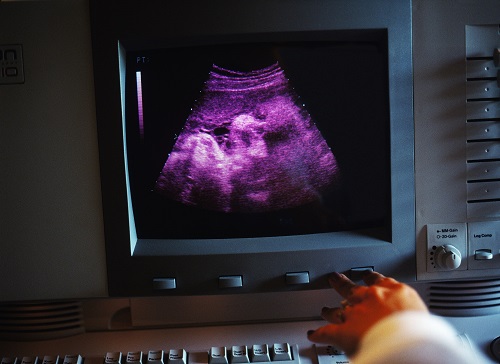

Mengimbau semula kejadian hitam itu, seorang budak perempuan berusia 8 tahun hanya diketahui hamil setelah kandungannya memasuki tempoh 8 bulan. Ekoran fizikal badan kecil, ibu bapanya menyangka anak mereka hanya mengalami masalah kembung perut. Setelah ditanya lanjut, akhirnya kanak-kanak ini membuka cerita.

Janin dalam perut boleh dijadikan bukti

Disebabkan jenayah itu berlaku tanpa saksi, polis agak sukar untuk merungkai kes tersebut. Mereka akhirnya merujuk kepada kepakaran Dr Djaja Surya Atmadja selaku pakar forensik. Kanak-kanak itu dibawa ke Jakarta dan beliau segera mengambil sampel air ketuban untuk disepadankan dengan DNA si pelaku. Keputusan analisis menunjukkan padanan yang tepat, sekali gus mengesahkan suspek berkenaan sebagai pelaku.